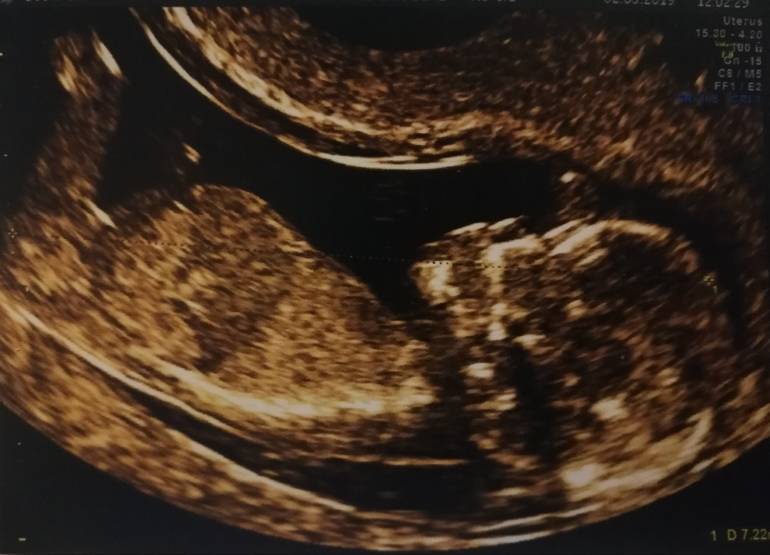

Witam w 19 tygodniu ciąży dowiedziałam się ze będę miała dziewczynkę w 20 tyg okazało się jednak , że to chłopak. Sama już nie wiem bo na jednym usg widać na pewno dziewuche a na drugim chłopca. Może to pempowina ?? Może ktoś mi pomoże rozwiązać ta zagadkę

Załączniki

• 4A8F5FF1-76CA-4DE0-AC12-5EDF08E820F2.jpg

4A8F5FF1-76CA-4DE0-AC12-5EDF08E820F2.jpg

596,4 KB · Wyświetleń: 43 546